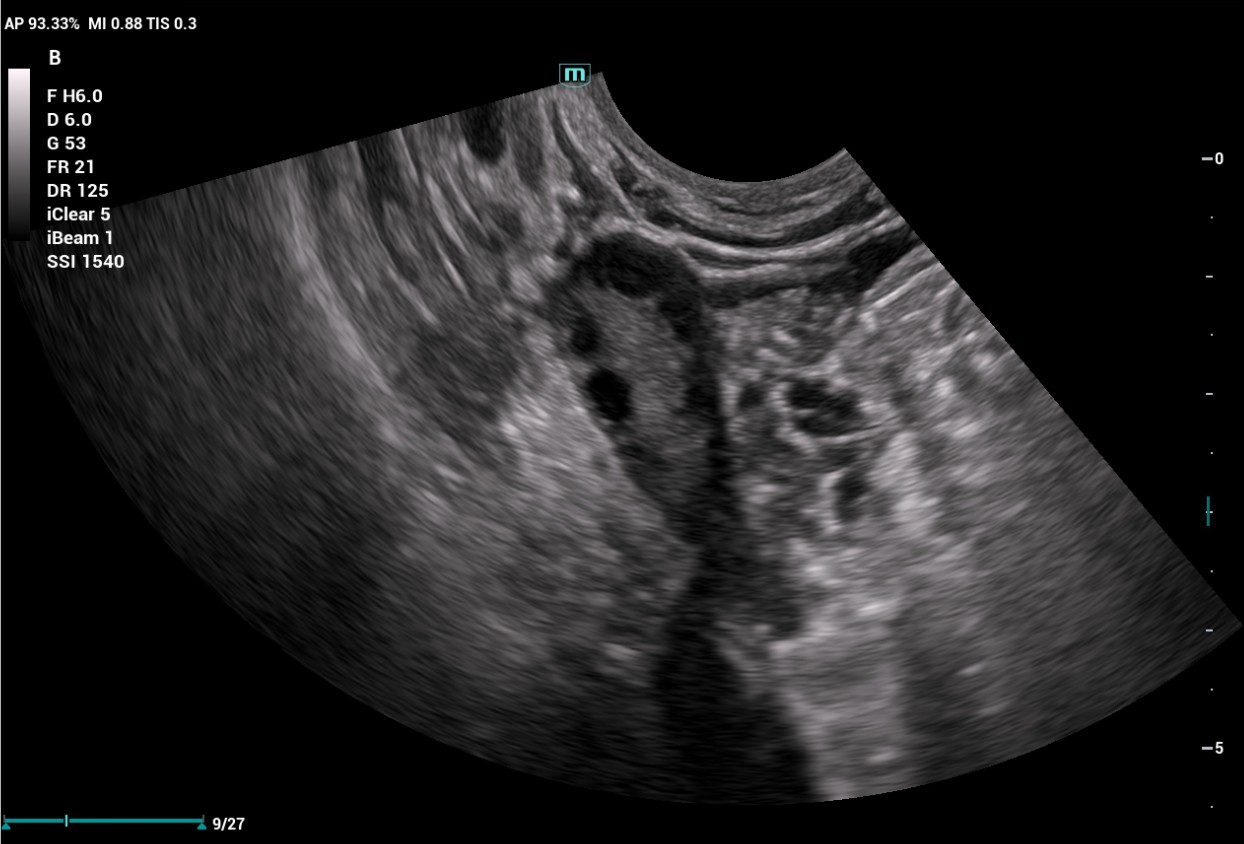

The Consona features new and concrete solutions, that efficiently help you to carry out smooth diagnoses for extensive type of patients. You will find highly powerful tools available on this series to keep you stay ahead in Obstetrics and Gynecology diagnosis.

Image Gallery